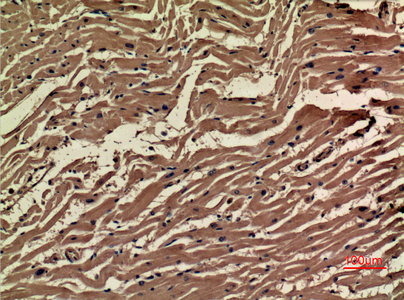

Immunohistochemistry analysis of paraffin-embedded Human heart using VEGFA antibody.High-pressure and temperature Sodium Citrate pH 6.0 was used for antigen retrieval.

Immunohistochemistry analysis of paraffin-embedded Human heart using VEGFA antibody. High-pressure and temperature Sodium Citrate pH 6.0 was used for antigen retrieval.